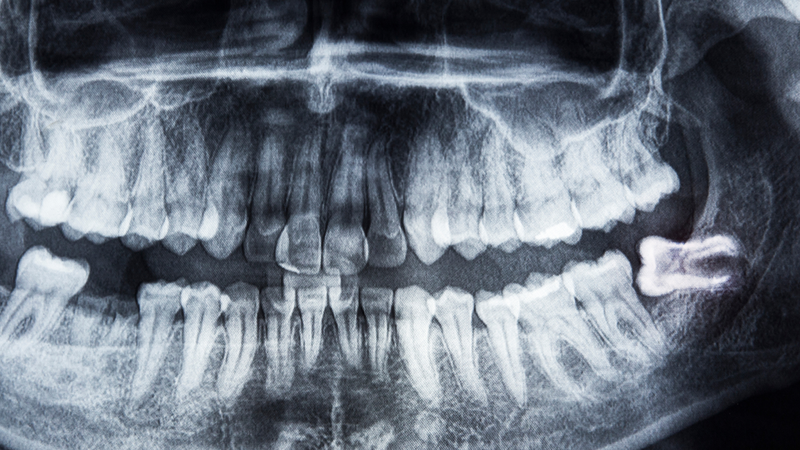

Lúc này, việc xử lý không còn đơn giản mà có thể phải can thiệp ngoại khoa, đồng thời theo dõi hậu phẫu cẩn thận để phòng biến chứng. Do đó, thăm khám răng định kỳ và chụp X-quang kiểm tra hướng mọc răng khôn từ sớm là bước quan trọng để bảo vệ sức khỏe răng miệng lâu dài.

Dù không thể ngăn hoàn toàn, nhưng việc khám răng định kỳ từ tuổi 17 trở đi giúp phát hiện sớm hướng mọc bất thường. Phim X-quang hỗ trợ chẩn đoán và lên kế hoạch xử lý trước khi răng gây biến chứng.